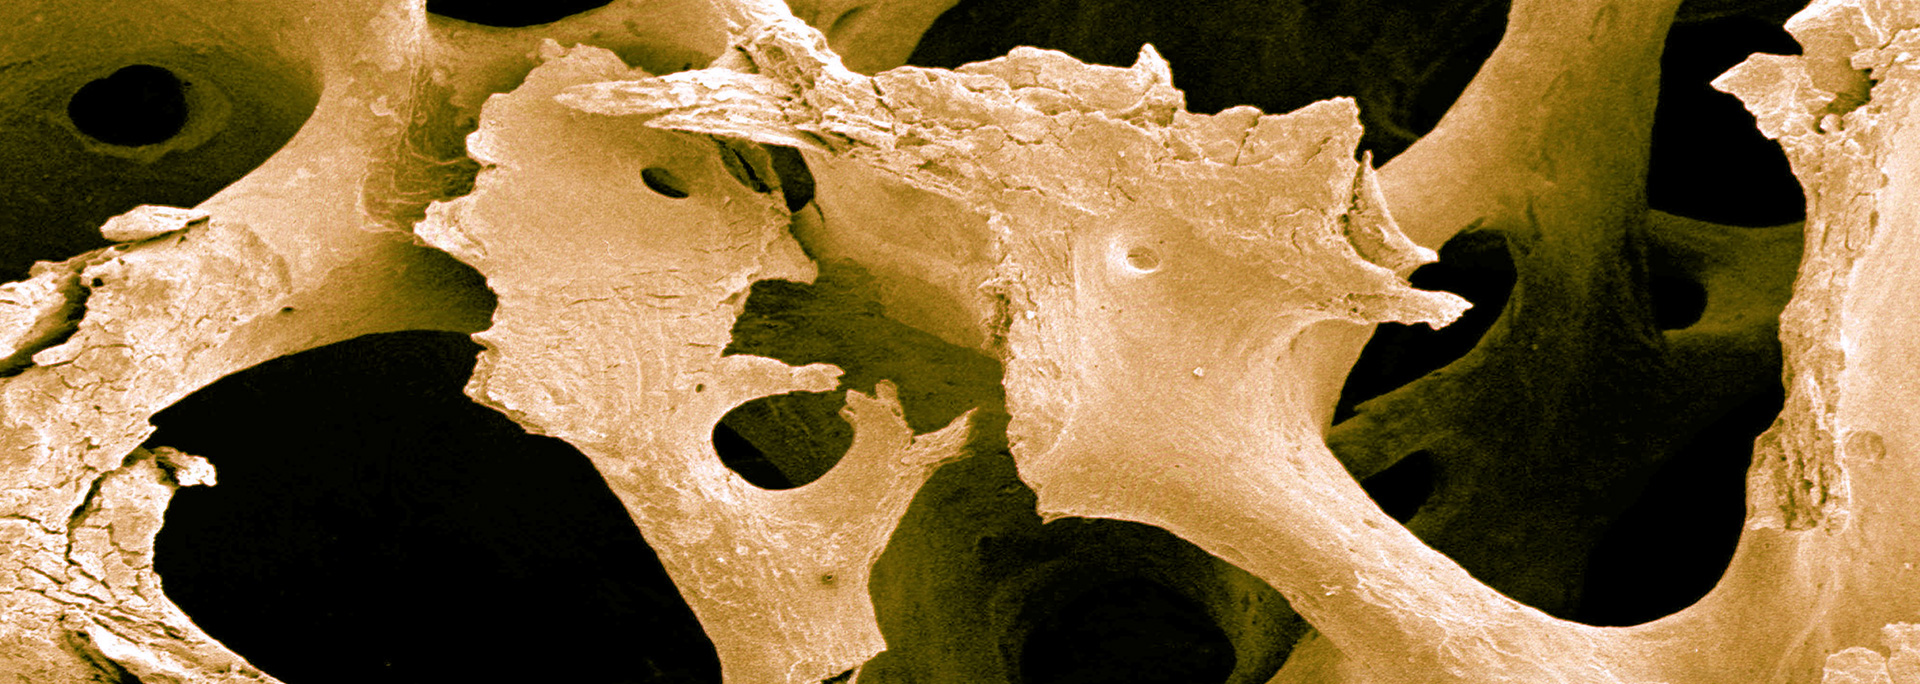

Eine sichere & effektive Behandlung zur Stärkung von Knochen & Muskeln ...

Für Menschen mit Osteoporose oder für Menschen, die dies vermeiden wollen ...

Durch sehr geringe Vibrationen werden Muskel und Knochen (wieder) aktiviert ...